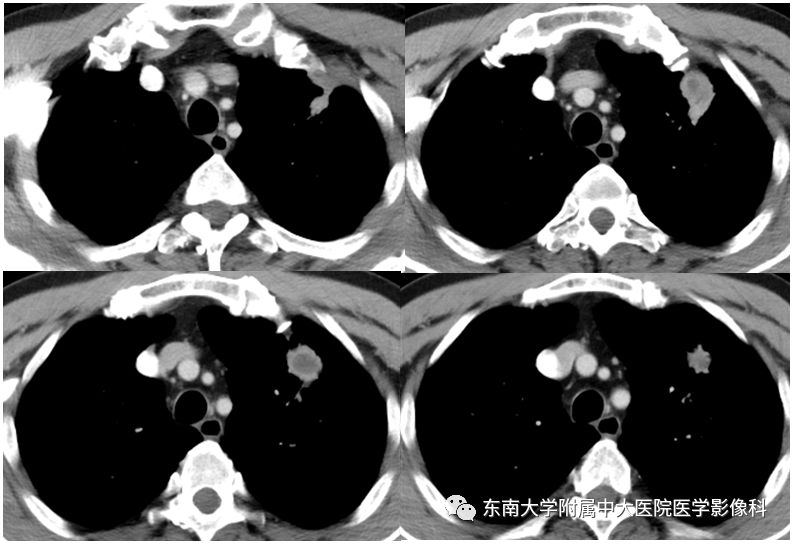

男,70岁,因“腹痛2月余,发现胃窦病变9天”入院

病例结果:病例1:机化性肺炎;病例2:肺腺癌